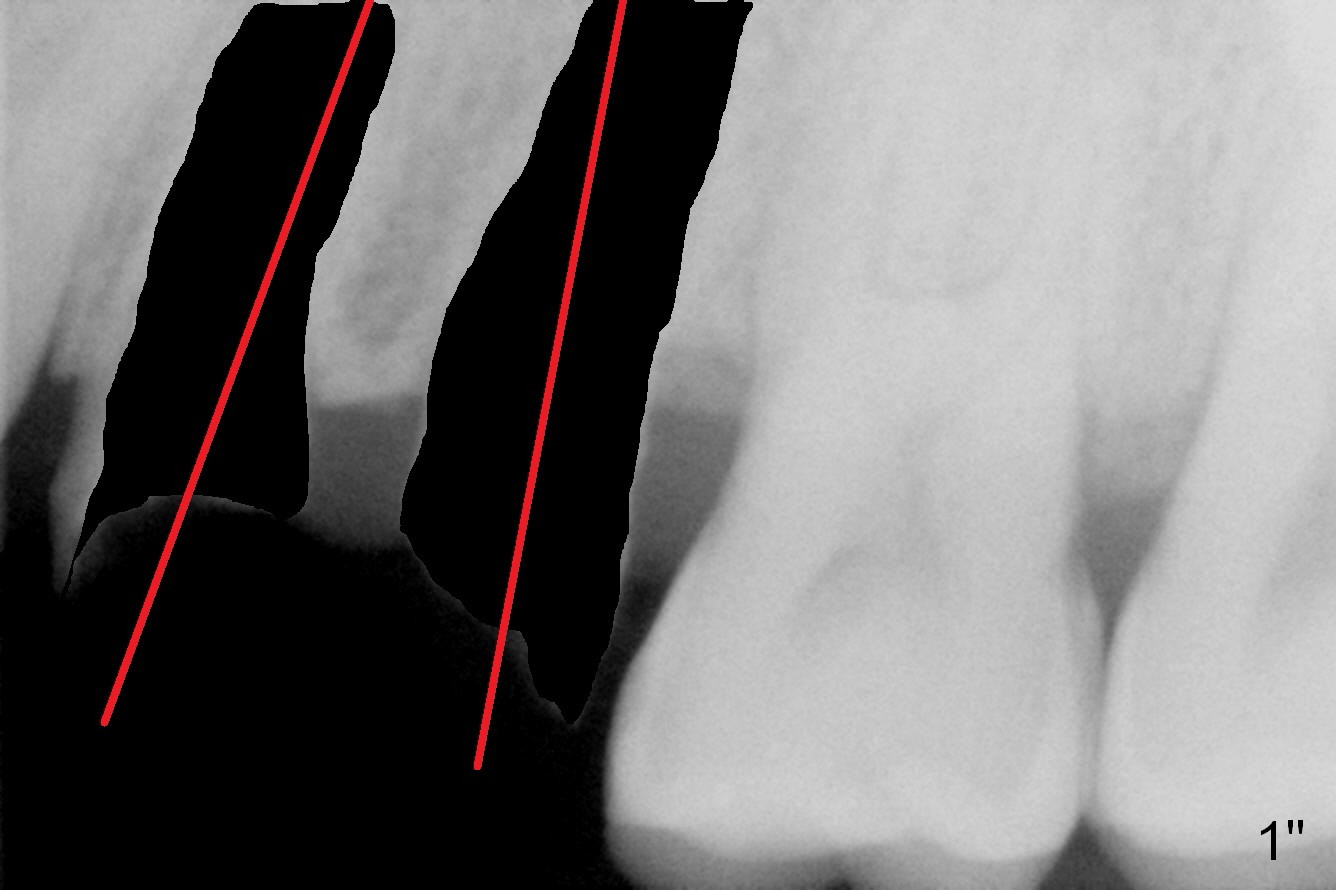

After extraction, osteotomy should not be at the center of the socket (Fig.1").